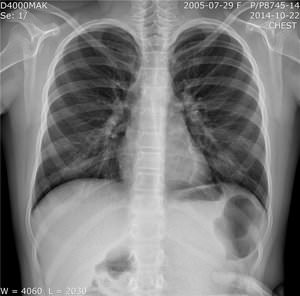

Если легкие у человека полностью здоровы, то нормальный легочный рисунок представляет собой картину циркулирующей по венам и артериям крови. Лимфатические узлы или бронхи не принимают участия в тенеобразовании. Рисунок хорошо просматривается в прикорневой зоне, где максимальный диаметр сосудов, с постепенным ослаблением к периферии, становясь еле видимым.

Усиление легочного рисунка на рентгене является важным диагностическим признаком, который может указывать на различные заболевания легких. Врачи отмечают, что это явление связано с изменениями в легочной ткани, такими как отек, воспаление или наличие патологических процессов. Увеличение сосудистого рисунка может свидетельствовать о сердечно-сосудистых заболеваниях, таких как сердечная недостаточность, в то время как усиление бронхиального рисунка может указывать на хронические заболевания, такие как бронхит или астма. Специалисты подчеркивают, что для точной интерпретации рентгенограмм необходимо учитывать клиническую картину пациента и результаты дополнительных исследований. Правильная диагностика и своевременное лечение могут существенно улучшить прогноз для пациента.

Нормальный легочный рисунок может измениться, если имеются патологии органов средостения и заболевания легких. Связано это с тем, что вокруг кровеносных сосудов возникает воспаление, вызывая утолщение их стенок, что обязательно отражается на рентгенограмме. В тенеобразовании начинают принимать участие и стенки бронхов – происходит их утолщение, между соединительной тканью возникают прослойки, которые в норме должны отсутствовать.

Благодаря тому, что вид у лимфатических и кровеносных сосудов сильно извитой, то они становятся хорошо заметными. Такой усиленный сосудистый рисунок обычно наблюдается при различных заболеваниях, которые сопровождаются выраженными нарушениями гемодинамики:

Снимок с высокой достоверностью может изучаться только на томограмме высокого разрешения или рентгенограмме. Оптимальным считается назначение исследования, которое проводится лучами высокой жесткости, так как на таких снимках отлично наблюдаются все отделы легких. Чтобы уточнить диагноз, важна оценка рентгенограмм, которые сделаны в разное время, и динамическое наблюдение. Существует два вида изменения легочного рисунка – разрежение и усиление.